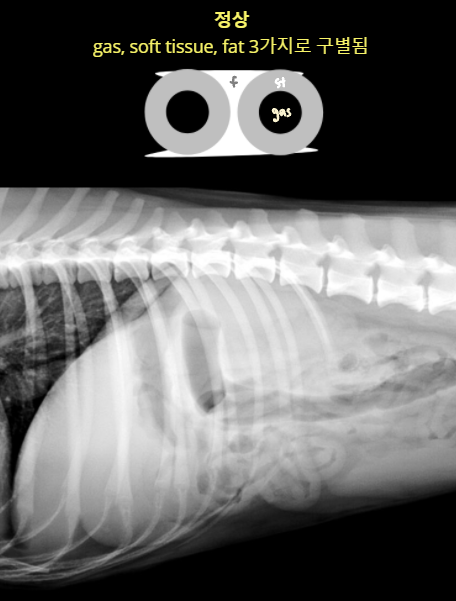

- gas, soft tissue(์ฐ๋ถ์กฐ์ง), fat(์ฅ๊ฐ๋ง) - ์ ์ contrast๊ฐ ๋ฌ๋ผ์ ์ฅ๋ฒฝ์ด ํ์ธ๋จ.

Serosal detail

- Serosal detail์ด ๋จ์ด์ง๋ฉด fluid๊ฐ ์ฐผ๋ค๋ ์๋ฏธ